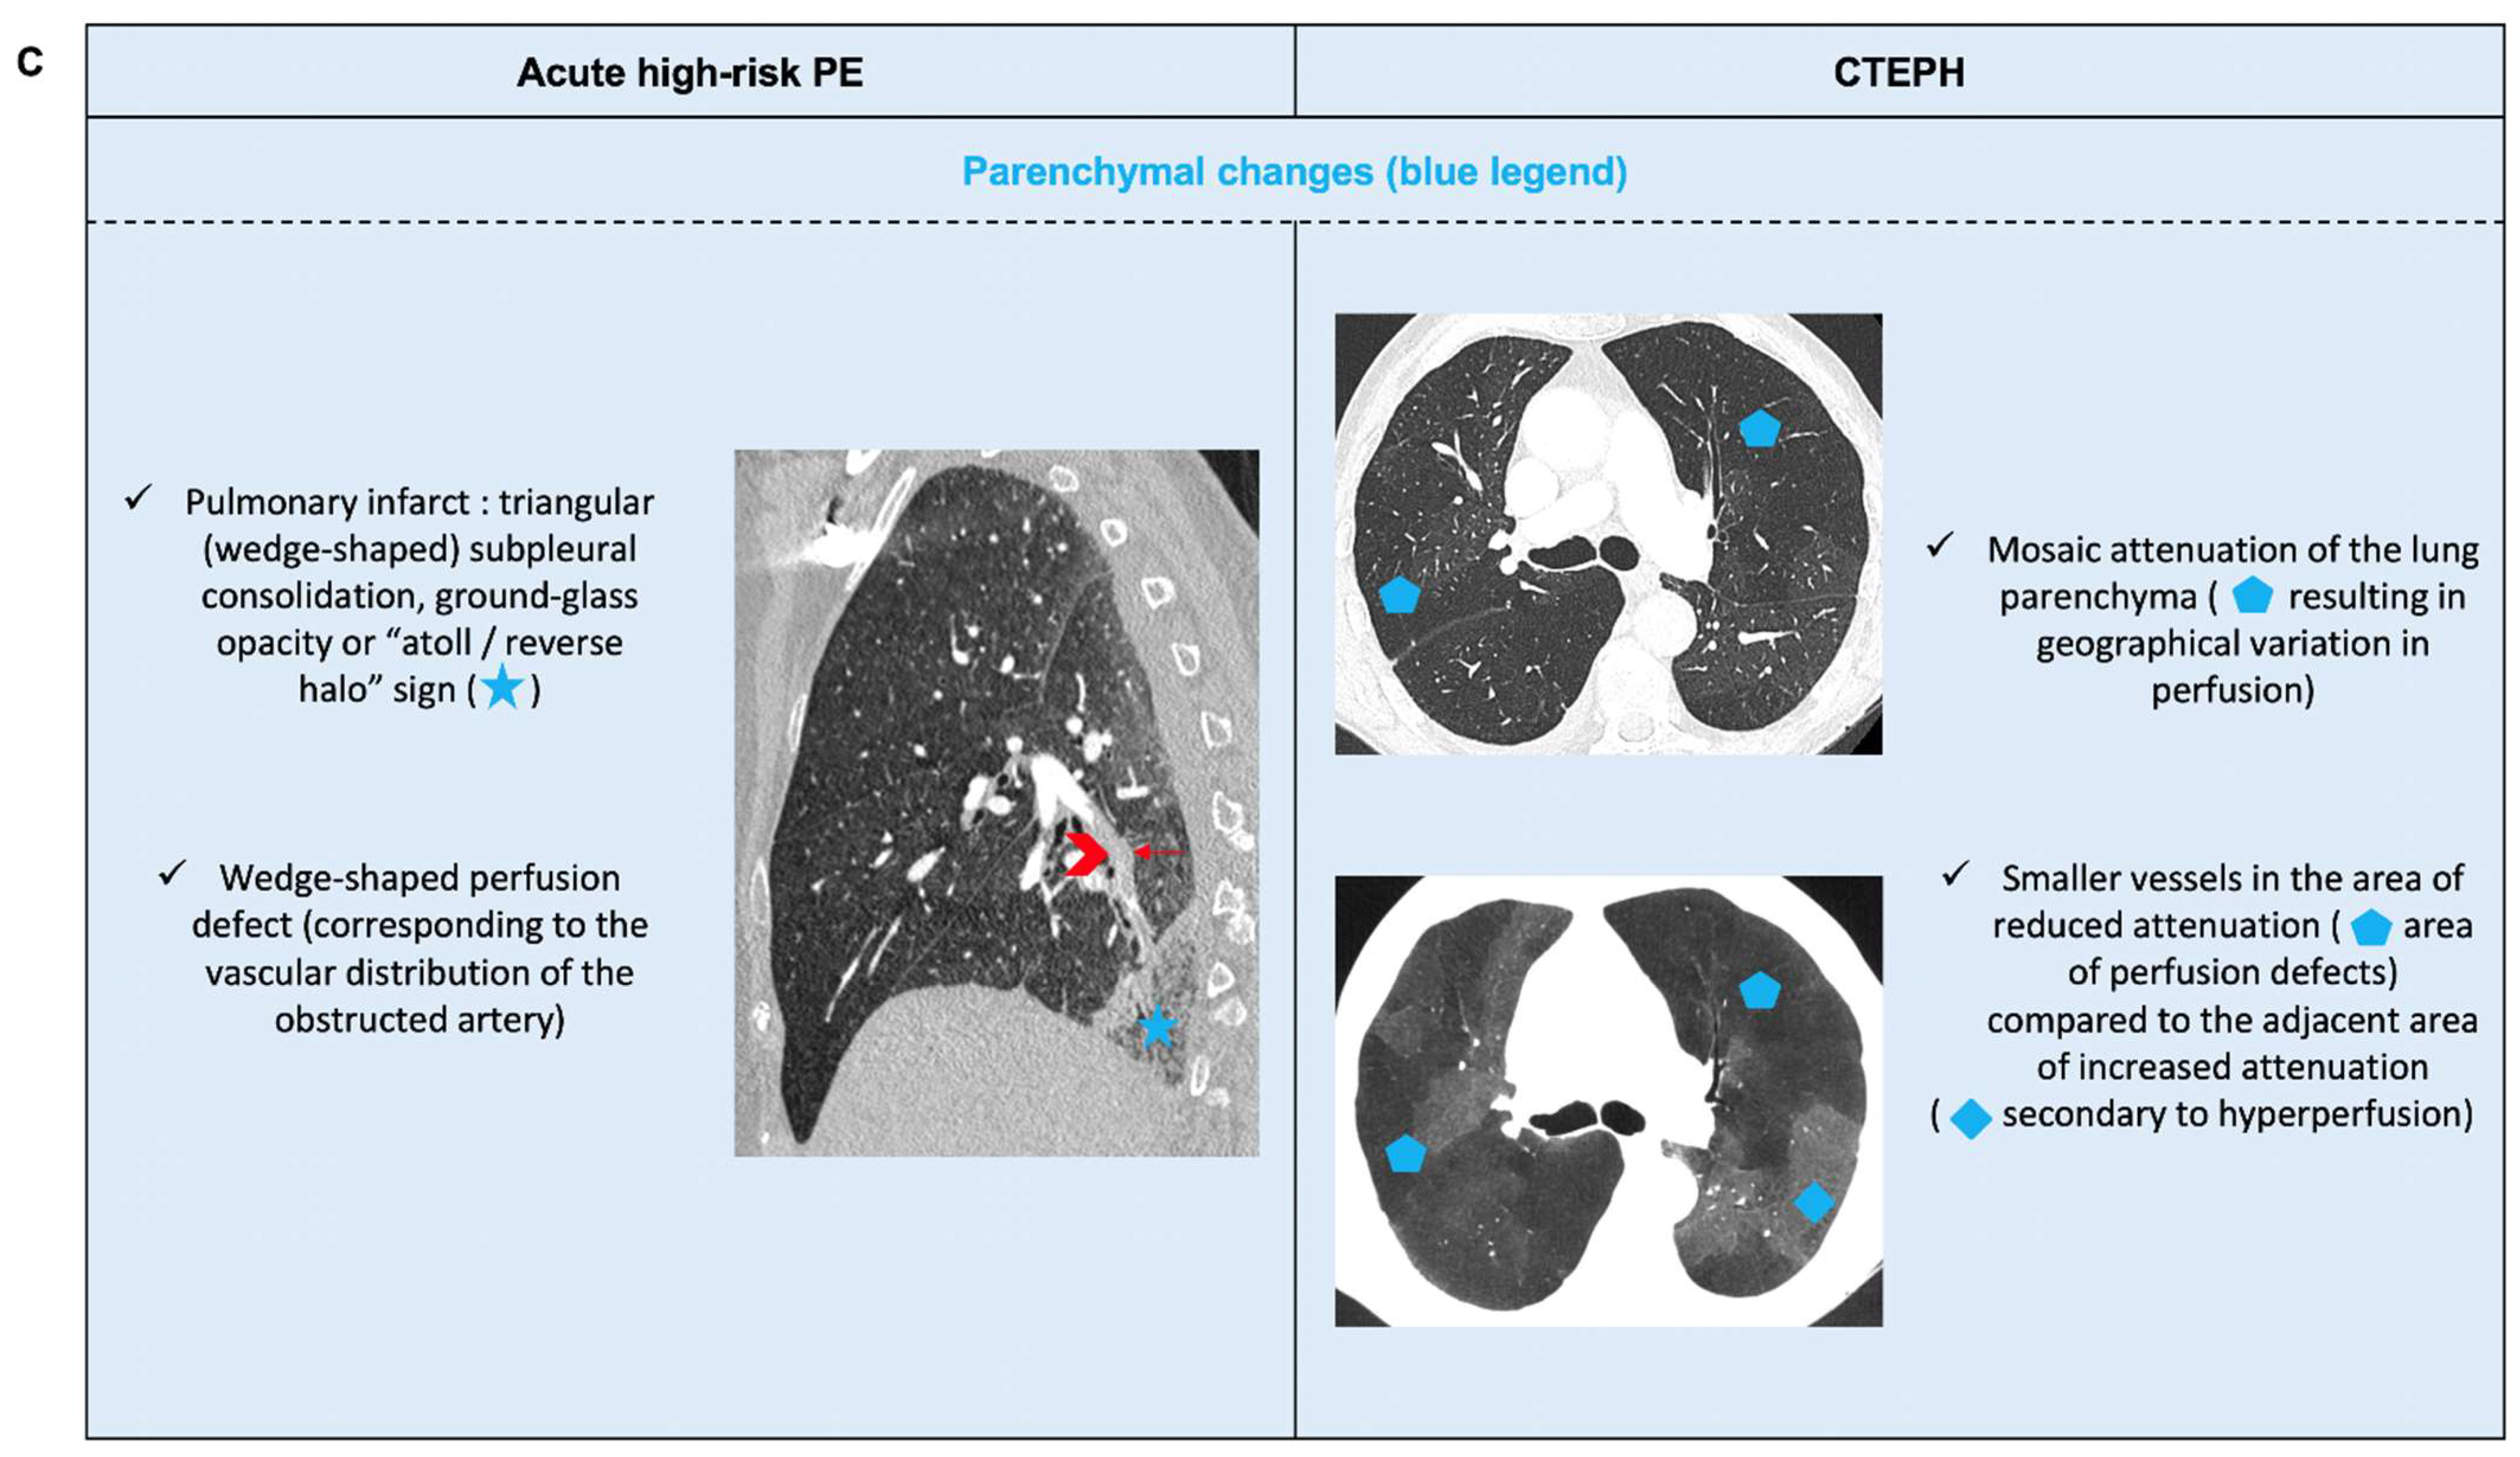

6.2. Acute PE with Underlying Chronic Thrombo-Embolic Pulmonary Hypertension